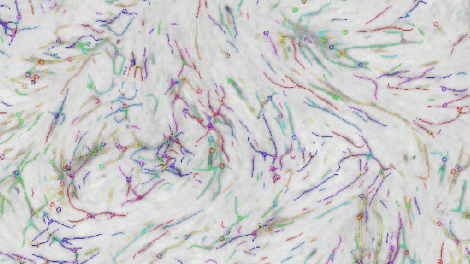

Angiogenesis: Testing the growth of new blood vessels.